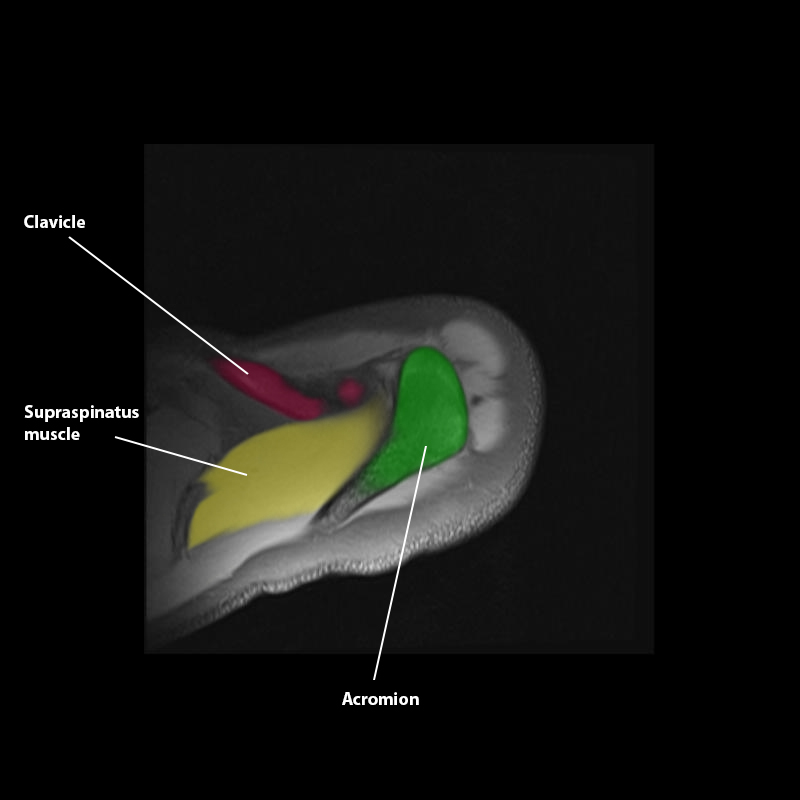

Shoulder MRI Anatomy